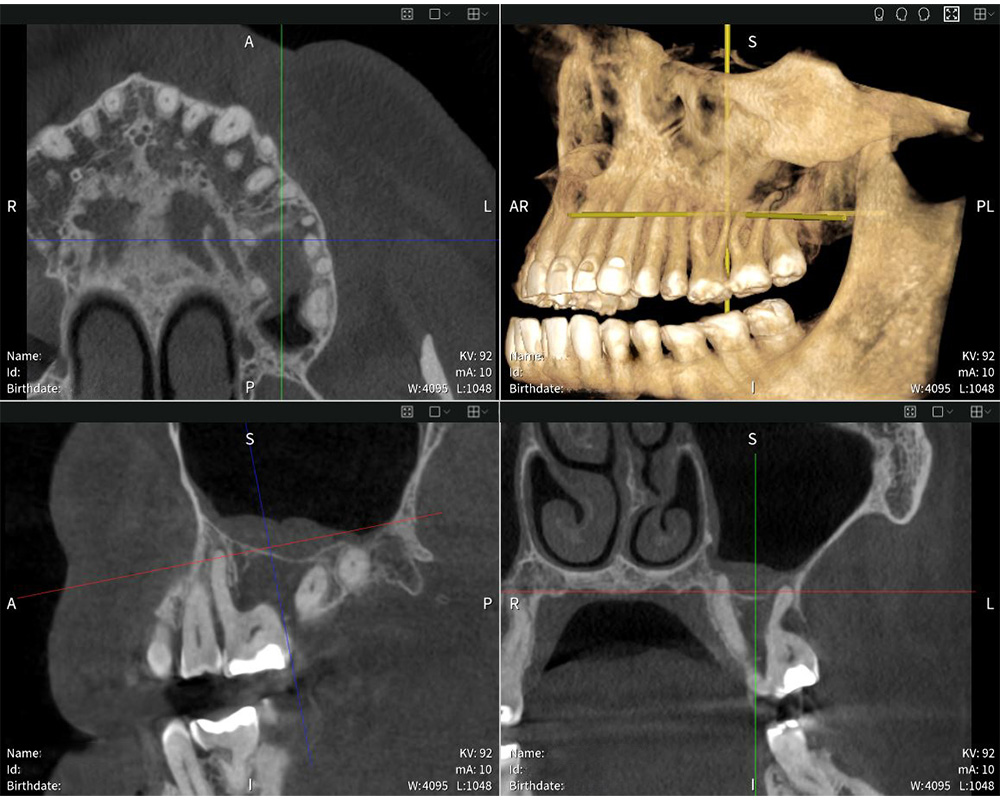

Seethrough Max und Seethrough Flex sind leistungsstarke DVT-Geräte.

Seethrough Max und Seethrough Flex sind leistungsstarke DVT-Geräte. © W&H

Seethrough Max setzt neue Maßstäbe in Sachen Benutzerfreundlichkeit. Das offene Design und die großzügigen Dimensionen bieten maximalen Komfort für Patient:innen und sorgen für eine besonders hohe Akzeptanz. Die Face-to-Face-Positionierung erleichtert zudem die Kommunikation zwischen Behandler:in und Patient:in. “Die Positionierung funktioniert ausgezeichnet. Ich schätze es, dass ich Patient:innen direkt gegenüberstehen und Blickkontakt halten kann. Das hilft mir, die optimale Patientenposition für einen präzisen Scan zu ermitteln”, so Dr med. dent. Mauro Amato. Ergänzend zur leistungsstarken Hardware sorgt Seethrough Studio für gestochen scharfe, detailreiche und unverzerrte Bilder. Ein fortschrittlicher Algorithmus zur Korrektur von Bewegungen verbessert die Bildqualität sowohl bei 3D- als auch bei 2D-Aufnahmen. Mit einem Field of View von bis zu 17 × 17 cm deckt Seethrough Max ein breites Anwendungsspektrum ab – von der Endodontie und Implantologie über die Oralchirurgie bis hin zur HNO – und das bei minimaler Strahlenbelastung. “Die Röntgenbilder überzeugen durch außergewöhnliche Schärfe und Detailtiefe, was eine exakte Diagnose und eine präzise Planung der Behandlung ermöglicht”, betont Dr med. dent. Mauro Amato.

Seethrough Studio sorgt für gestochen scharfe, detailreiche und unverzerrte Bilder.

Seethrough Studio sorgt für gestochen scharfe, detailreiche und unverzerrte Bilder. © W&H